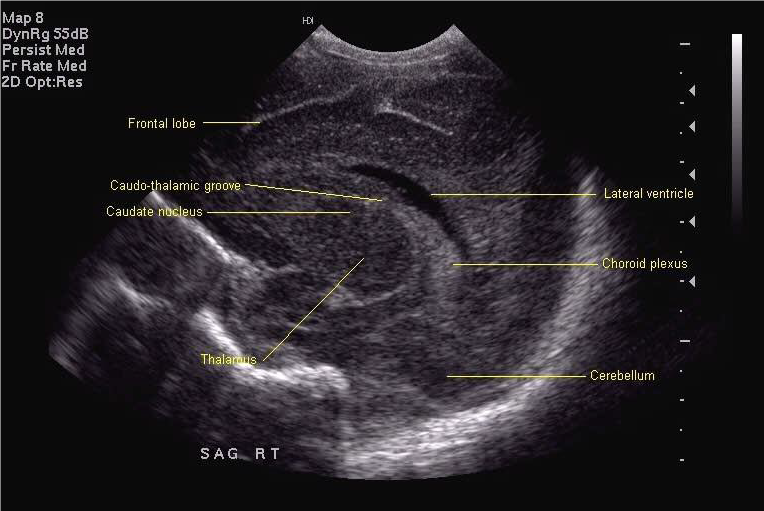

All scan results should be discussed with parents and, unless normal, this should be done by a member of the senior medical team. Although standard views for examination and hard copy print out are shown below, it is good practice to examine the peripheries of the brain including extreme lateral sagittal views, extreme anterior and posterior coronal views.

Lateral sagittal (to be labelled "left" or "right")